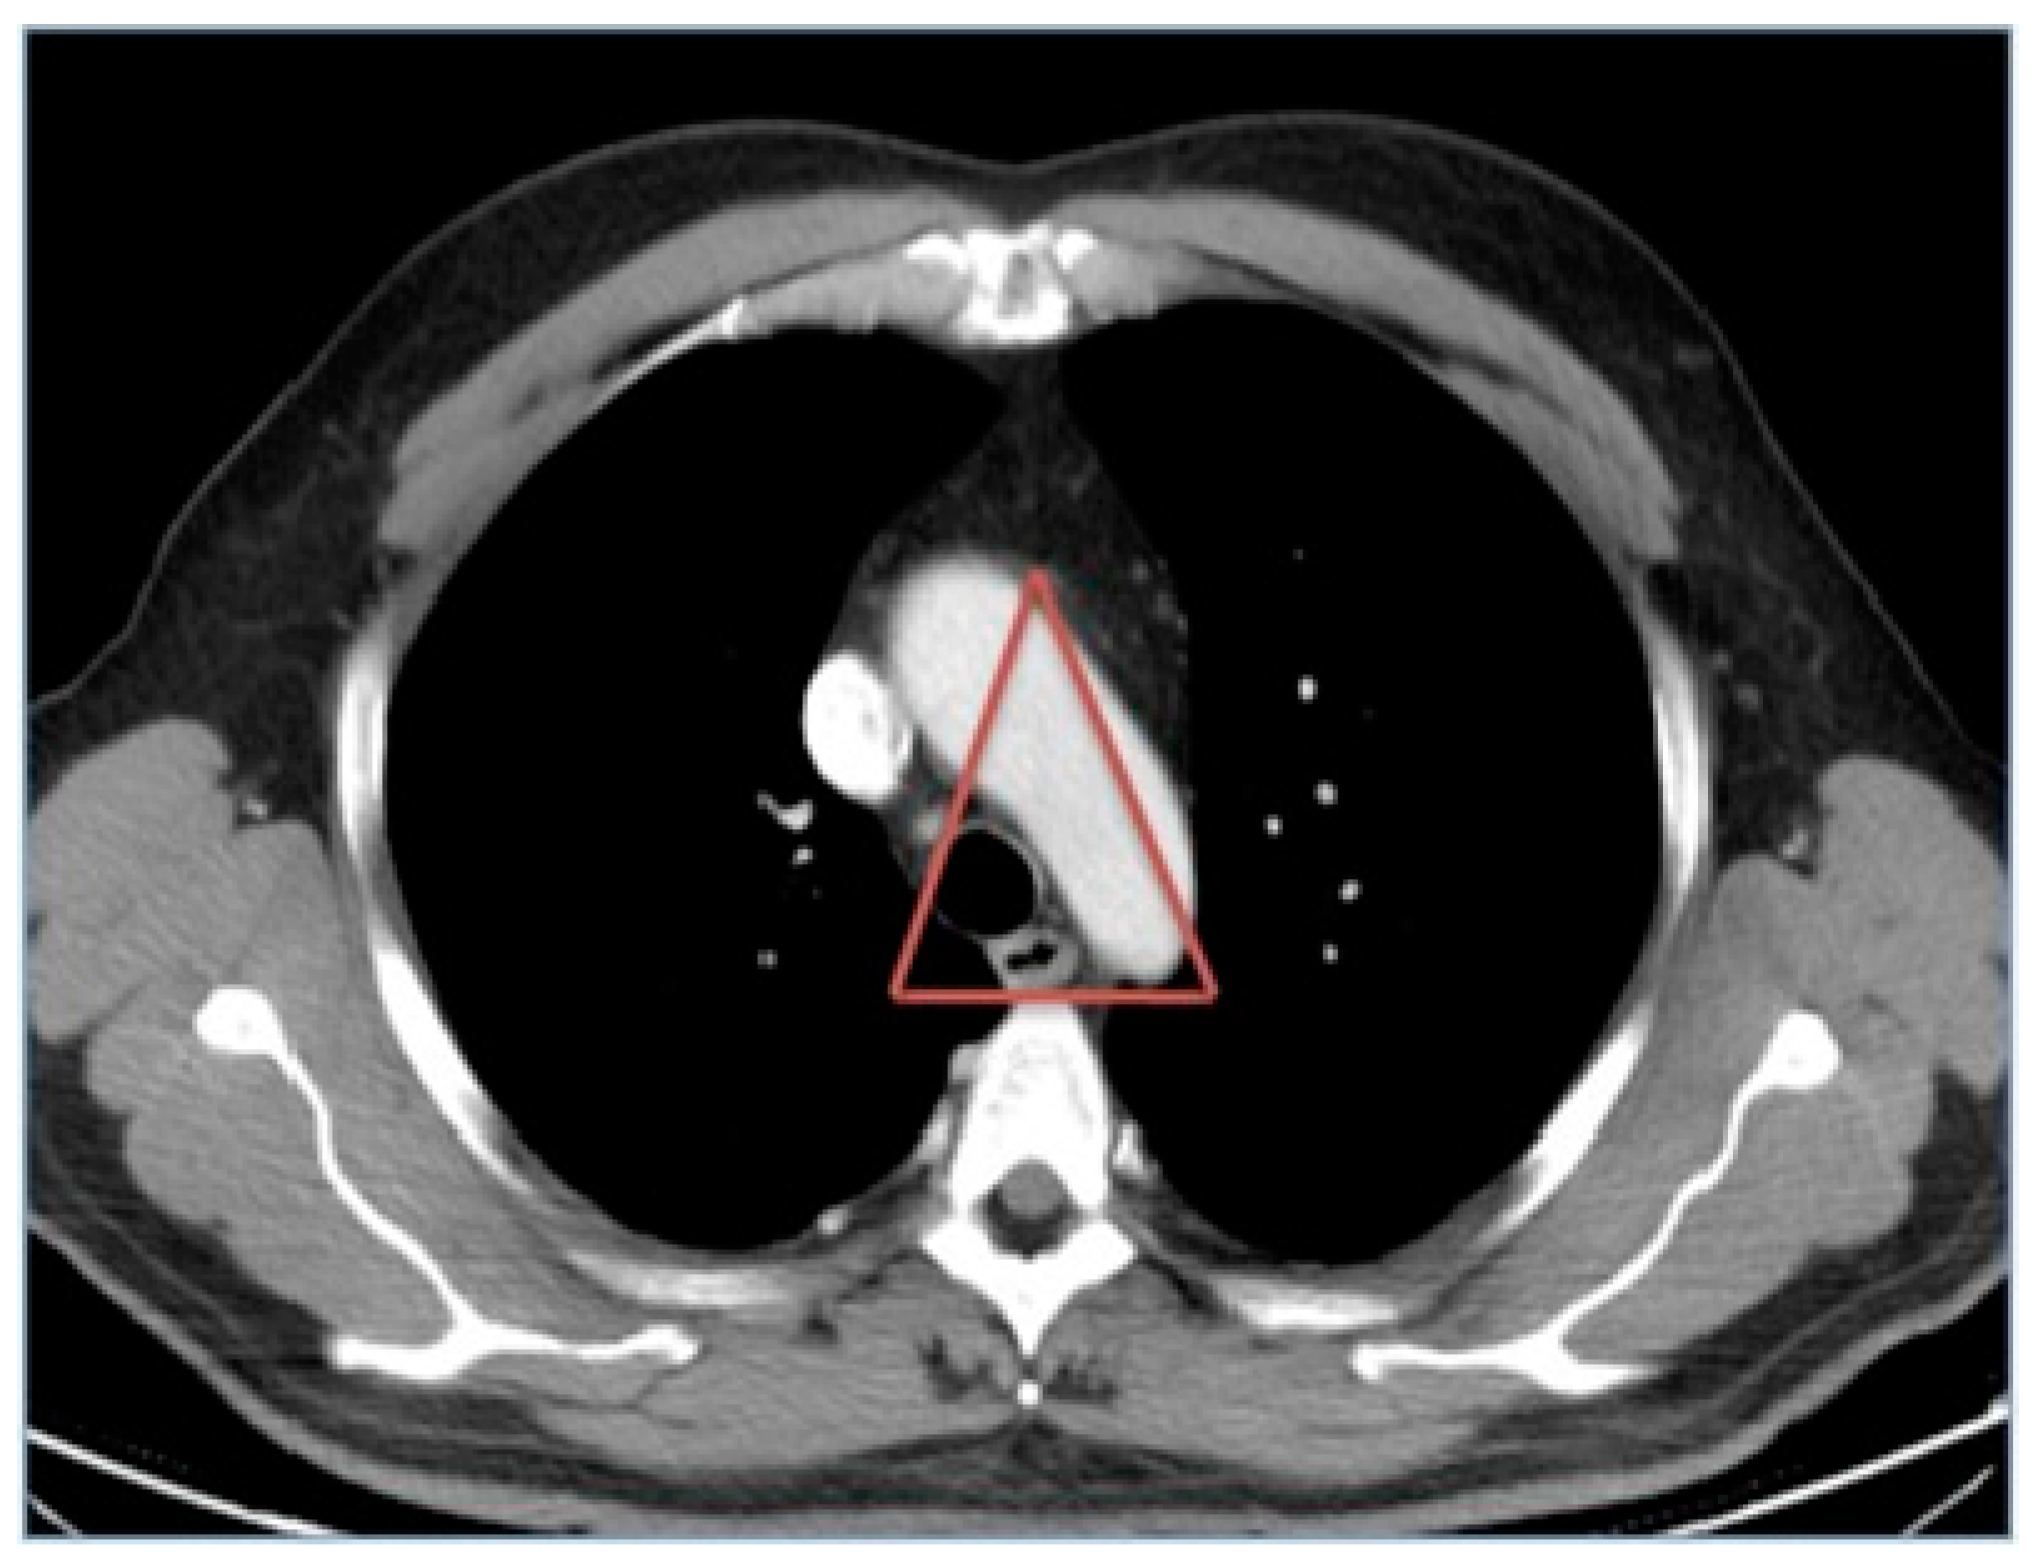

The Importance of the Mediastinal Triangle in Traumatic Lesions of the Aorta